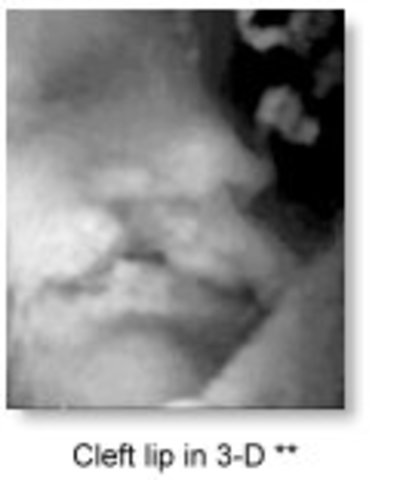

• 3D

3D

Kazunori Baba from Tokyo, Japan, first reported a 3-D ultrasound system in 1984 and succeeded in obtaining 3-D fetal images by processing the raw 2-D images on a mini-computer in 1986.

http://www.ob-ultrasound.net/history1.html